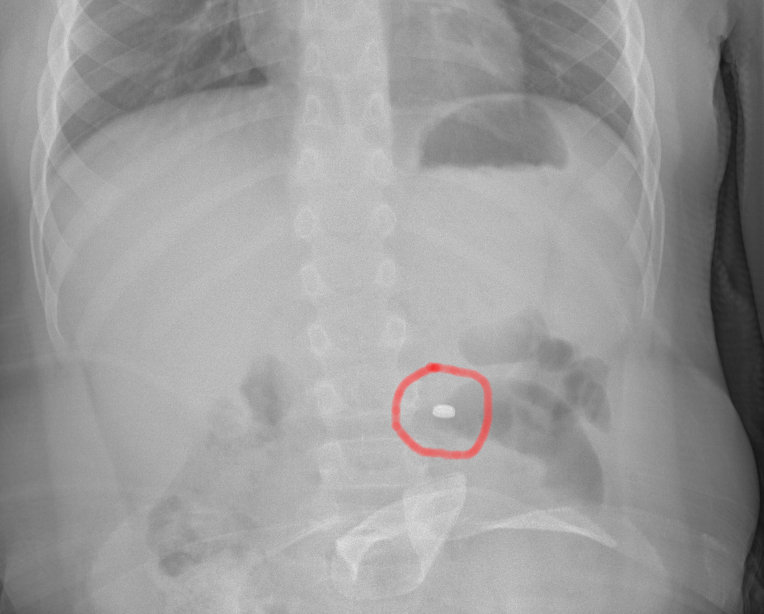

La famiglia, naturalmente spaventata, dopo una prima valutazione al PS della propria città, è stata indirizzata all’Ospedale Cannizzaro di Catania. Qui i medici hanno compreso il pericolo e applicato le linee guida riferite precisamente all’ingestione di una pila a bottone. Eseguita la radiografia dell’addome che ha messo in evidenza la presenza e la localizzazione del corpo estraneo, il bambino è stato condotto in sala operatoria dove gli endoscopisti, con l’assistenza degli anestesisti, hanno potuto estrarre in sicurezza il piccolo oggetto, prima che esso potesse causare conseguenze più importanti. Dopo una notte in osservazione, tornato in piena salute, il bimbo ha fatto rientro a casa con i genitori.